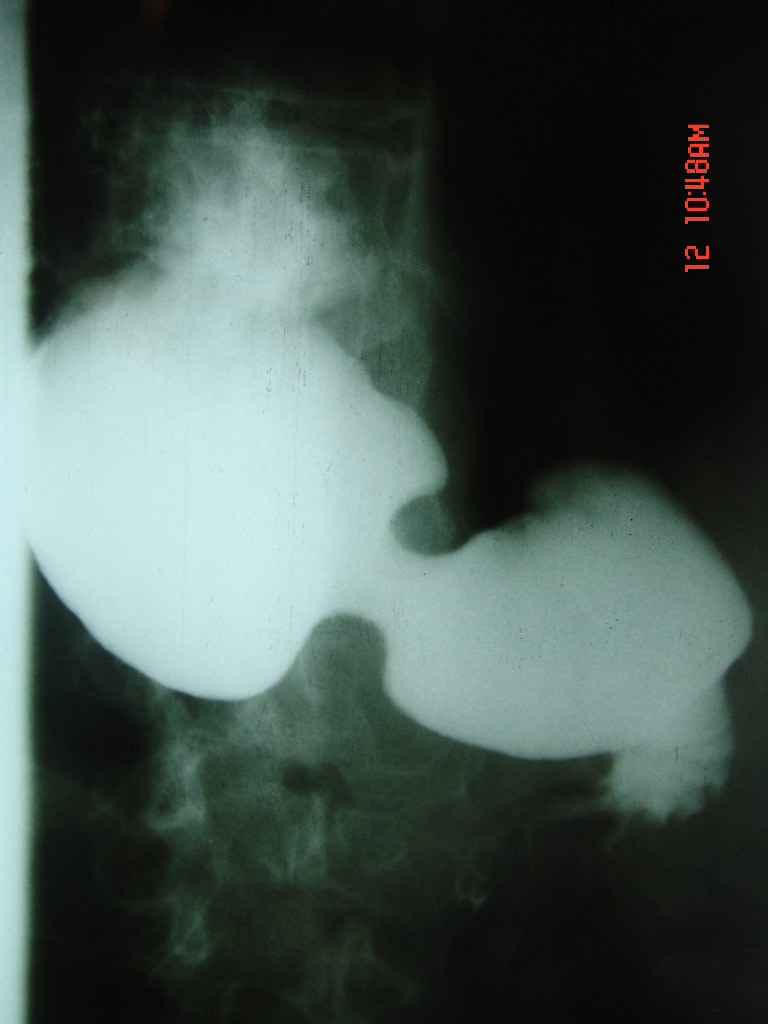

胃体部粘膜不规则增厚,胃肠造影也显示充盈缺损-胃溃疡?胃癌?

上消化道造影见十二指肠结节状充盈缺损,ct增强十二指肠壁局限性增厚并强化,考虑十二指肠壶腹癌?